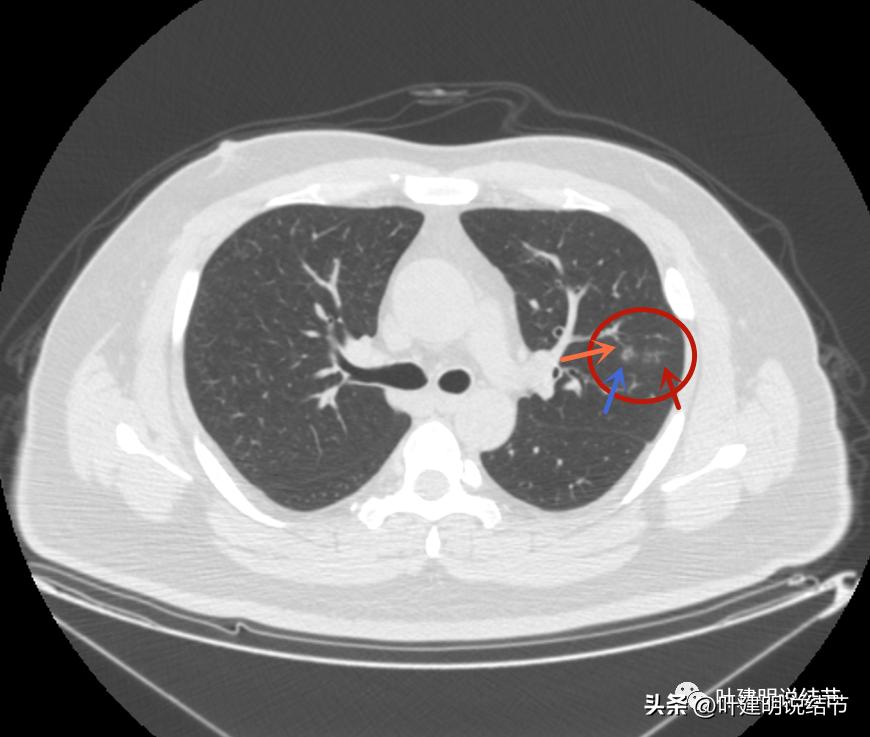

左上病灶2与左上病灶3:

病灶2出现,还只有一点点磨玻璃影,血管走行有点异样

密度略显高,有微血管进入(桔色箭头),边缘略模糊,但轮廓还是较清

中间有实性成分出现(粉色箭头),微血管进入明显(桔色箭头),边上有磨玻璃成分(绿色箭头),整体轮廓清

病灶密度不均

密度不均显杂乱

表面略不平

整体瘤肺边界与轮廓较清

边上另有病灶出现,即左上病灶3(蓝色箭头)

病灶3也有微血管进入(桔色箭头)